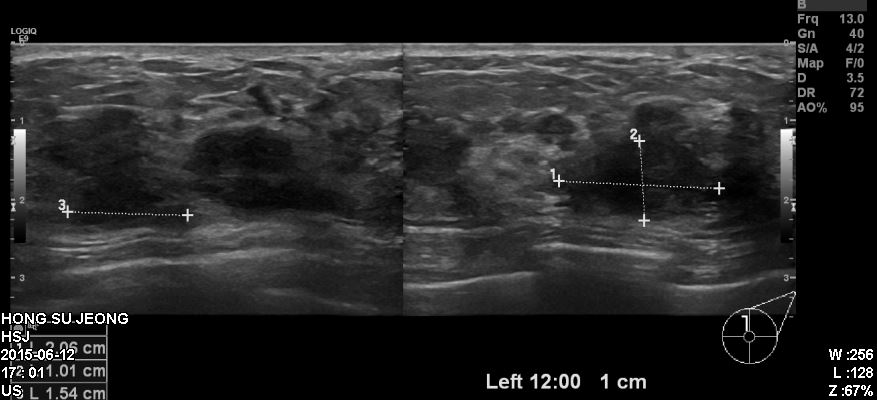

건진상 이상소견으로 내원하신 50대 환자분이십니다.

타원유방초음파상 확인되는 좌측유방12시방향의 혹과 좌측겨드랑이에 부어있는 임파선을

조직검사 하였고 결과상 침윤성 유관암진단되었습니다.